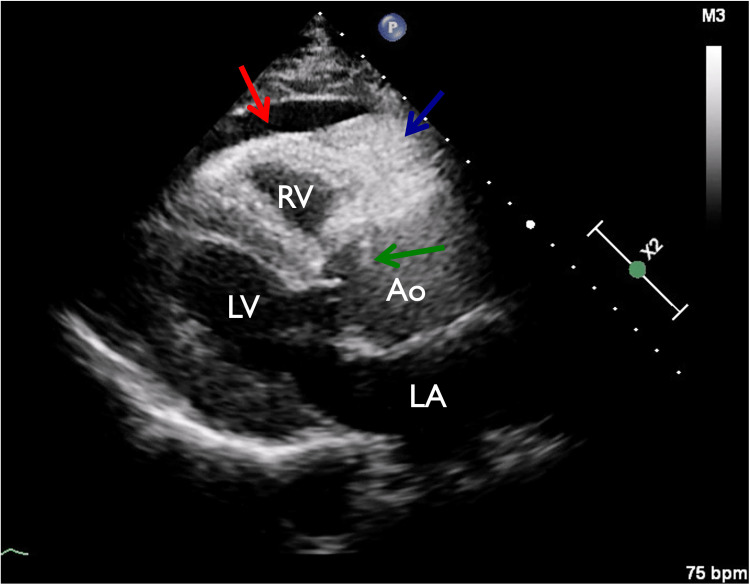

In view of chest pain associated with positive cardiac biomarkers, he was admitted to the Coronary Care Unit on intravenous nitroglycerin. While waiting for his admission, he suddenly had recurrent chest pain associated with marked hypotension (75/43 mmHg), for which the intravenous nitroglycerin was discontinued, fluid resuscitation was provided, and he was temporarily started on intravenous norepinephrine. The on-call cardiology team was contacted for an emergent evaluation. Subsequent ECG showed nonspecific ST-segment changes in leads V5-V6 (Figure 1). An emergent bedside echocardiogram revealed a moderate pericardial effusion of hemodynamic significance (Figure 2), as suggested by partial right ventricular chamber collapse (Figure 3) early in diastole and a plethoric non-collapsing inferior vena cava. The pericardial effusion also contained echogenic strands, which are highly concerning for blood clots. Additionally, a moderate to severe aortic valve insufficiency (Figure 4) was present according to color Doppler findings and pressure half-time assessment (315 ms). An intimal flap was visualized on the ascending and descending aorta, suggesting an extensive AD (Figures 2–6). A computer tomographic angiogram (CTA) of the chest and abdomen revealed a large pericardial effusion with an extensive AD extending from the level of the ascending aorta into his right brachiocephalic artery, the right and left common carotid arteries, and inferiorly to the right iliac artery (Figures 7–10), although not occlusive in diameter (or clinically). These findings were consistent with an extensive Stanford type-A AD with rupture into the pericardium, for which volume expansion and vasopressors were provided and emergently operated on the same day. The surgery included an open pericardiotomy with pericardial blood drainage, replacement of the ascending aorta from just above the commissure to the take-off of the innominate artery, partial replacement of the aortic arch, and aortic valve repair with successful results. Multiple intraoperative packed red blood cell units (8), fresh frozen plasma units (4), cryoprecipitate units (10), and platelet apheresis (3) were provided in view of bleeding complications related to the arrival provision of dual antiplatelet and anticoagulation therapy prior to the diagnosis of AD.